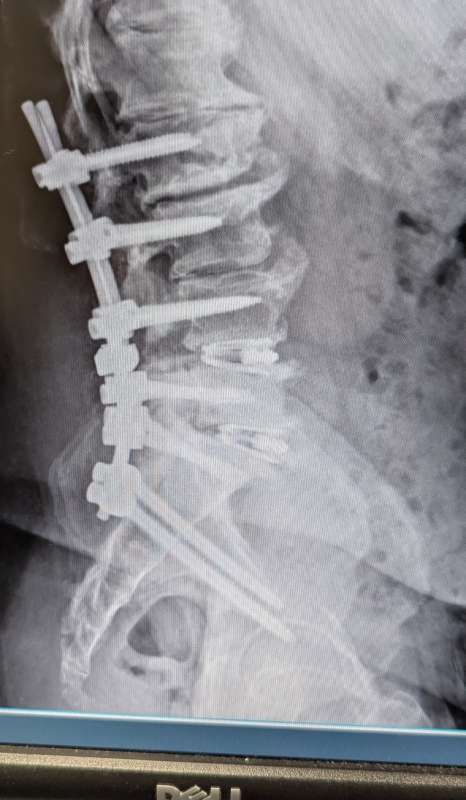

I just returned home from my first post surgery visit with my back surgeon.

Turns out he had to add a lot more hardware than originally anticipated.

I ended up with

14 screws

6 rods

2 cages

I'm 2 weeks out now and still sore, but it's getting better every day.

It going to be a long time before I know what my physical limitations will be..

Here's a couple pics or what my spine looks like as of this morning